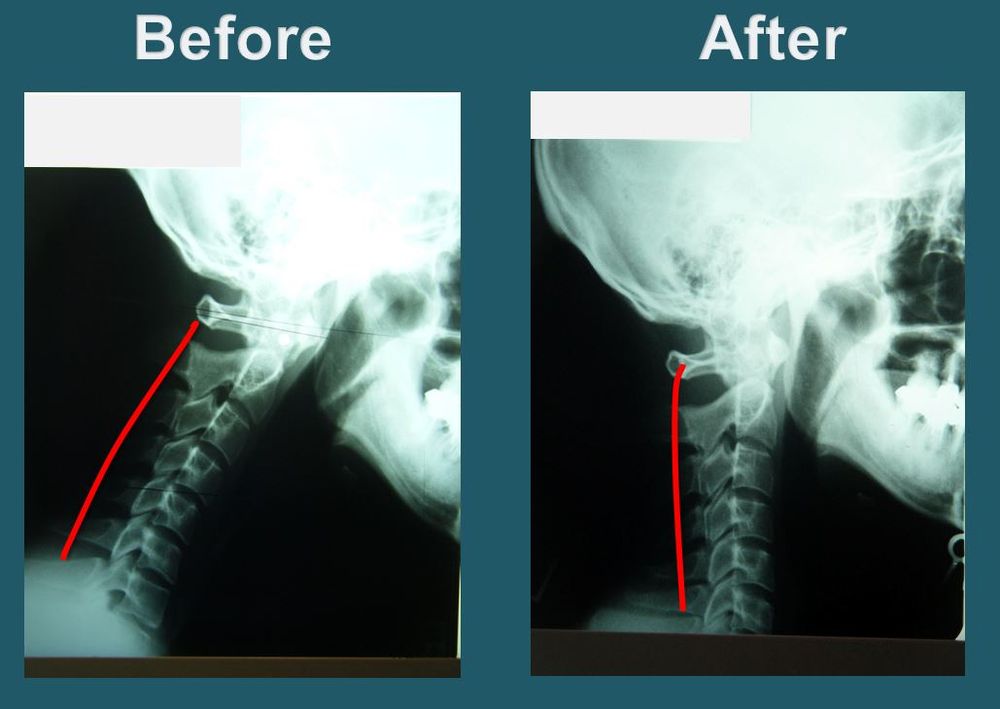

Upper Cervical Corrective Health Care is an effective, scientifically proven specialty in the Chiropractic profession. The procedure is designed to restore head/neck alignment to remove interference at the point where the head and neck join. With this procedure, Dr. Park seeks to re-activate the brain to body communication so the body’s natural self-healing process can begin!

Dr. Park will take X-rays of the upper cervical region, neck, full spine, and pelvis to observe and examine the degree of misalignment. The doctor will then implement the procedure to restore head, neck and spinal alignment. This procedure is performed by the doctor’s own hands, without the use of any needles or electric therapy.

As soon as the vertebrae is aligned correctly, the brain will immediately start sending healing messages to those parts of the body affected by the misalignment and begin the natural self-healing process. Blockage of brain to body messages can be the direct or indirect cause of most health problems. On each visit, Dr. Park seeks to regain and maintain the proper alignment of the spine, aiding each patient through the process of recovery and healing.